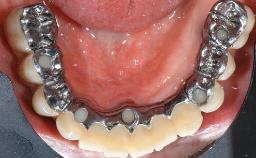

This case describes the ongoing management of a 64-year-old healthy, non-smoking female patient with erosive oral lichen planus (OLP) affecting the gingivae and the buccal and lingual mucosa. The peri-implant mucosa was also affected subsequent to implant placement. The patient had osseointegrated implants (four in the maxilla, four in the mandible) placed following extraction of hopeless teeth and a healing period. The patient had a history of OLP prior to implant placement and had been referred to an oral-medicine specialist for definitive diagnosis and treatment. She exhibited generalized oral mucosal involvement. Following a clinical assessment, biopsy, and blood tests, she was treated with topical corticosteroids. Systemic prednisolone was reserved for severe flare-ups. Amphotericin lozenges were used in combination with corticosteroid treatment to prevent the development of oral candidiasis.

# of Implants 8

Type of Implants Two-Piece

Prosthesis Type FDP